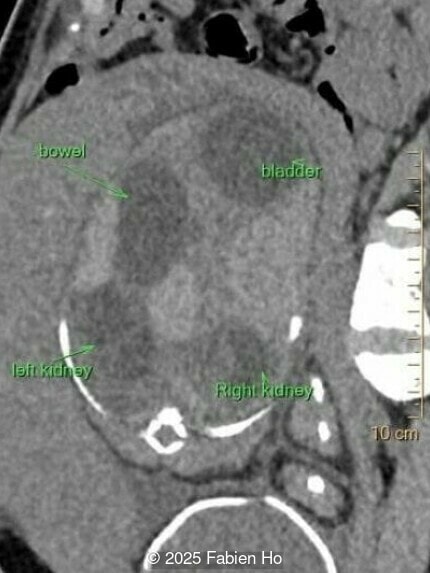

At 36 weeks gestation, the abdominal findings were unchanged however, the bones appeared short (<1st percentile) and the spine had an unusual appearance, therefore a computed tomography was performed at 37 weeks gestation.

Axial image of the abdomen

Image 7 Axial image of the abdomen

Our prenatal ultrasound revealed a male fetus with megabladder, dilation of both ureter and kidneys, and thinned kidney parenchyma consistent with Lower Urinary Tract Obstruction (LUTO).  Additional findings suspected on ultrasound and confirmed on computed tomography included:

• Short long bones (<1st percentile), normal mineralization, and no sign of lethal chondrodysplasia

• Dysostosis: Hemivertebrae L3, fused L4-L5, abnormal left foot with short metatarsals and missing phalanges